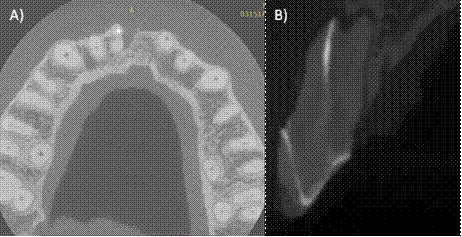

A la exploración clínica observamos una tumefacción de los tejidos en la zona anterosuperior y presencia de tracto sinusal, una restauración desajustada correspondiente a una corona libre de metal, invasión del espesor biológico, inflamación gingival, dolor a la masticación, percusión horizontal y vertical (Fig. 1B). En la radiografía periapical del órgano dental #11 (orto-radial y mesio- radial) observamos lesión radiolúcida en la raíz a nivel apical y mesial, perdida de la cresta ósea interproximal y lamina dura no visible. En la porción apical observamos una subobturación (Fig. A,C). Se realizó una TCHC y al observar la tomografía se confirmó la presencia de dos raíces en dicho órgano dentario de las cuales, solo la raíz vestibular estaba tratada endodónticamente (Fig. 2 A-B). Diagnóstico: Órgano dental previamente tratado con absceso apical crónico29. Se anestesio con articaína 4% con epinefrina 1:100 000 supraperióstica en fondo de saco anestesiando el nervio alveolar anterior, se eliminó la restauración coronaria utilizando una fresa de diamante y pieza de mano de alta velocidad, una vez retirada, se realizó aislamiento absoluto con dique de goma, se procedió a eliminar la gutapercha con limas Wave One Gold (Dentsply Sirona, Tulsa Dental), se exploró el conducto palatino con limas tipo K 6 y 8 hasta lograr permeabilizarlo, la longitud de trabajo de ambas raíces se obtuvo con la ayuda de localizador apical Apex ID (SybronEndo, Orange, CA)(Fig.3A), se instrumentó con limas Wave One Gold (Dentsply Sirona, Ballaigues, Switzerland ) Large (45/05) para el conducto vestibular y médium (35/06) para el conducto palatino, la irrigación se realizó con hipoclorito al 5.25 % durante todo el tratamiento para finalizar con un protocolo de irrigación de 3 ciclos de 20 segundos, hipoclorito de sodio 5.25%, agua destilada y EDTA 17% (Smear clear Sybron Endo, CA), activados con ultrasonido (Ultra X, Eighteeth Medical), se colocó hidróxido de calcio como medicación intraconducto durante 15 días. La segunda cita se realizó nuevamente protocolo de irrigación, los conductos se secaron con puntas de papel estériles y fueron obturados con técnica de onda continua de calor (Fast fill and Fast Pack, Eighteeth Medical) y cemento AH-Plus (Dentsply Maillefer, Ballaigues, Switzerland) (Fig. 3 B-C), por último, se utilizó resina fluida para el sellado del acceso coronal. Se solicitó una segunda TCHC para evaluar la correcta localización y obturación del órgano dental (Fig. 4 A-B).

Figura 2: A) Corte axial de la tomografía, podemos observar dos raíces pertenecientes al órgano dental #11, la raíz vestibular presentar material de obturación, pero la raíz palatina no fue tratada, B) Corte sagital donde se comprueba un conducto palatino permeable.